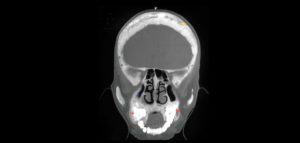

86 – Exactitud de los diferentes tipos de diseño de las guías quirúrgicas en la colocación de implantes

El número de pacientes que requieren prótesis sobre implantes ha aumentado considerablemente en los últimos años. La osteointegración de los implantes dentales es el requisito